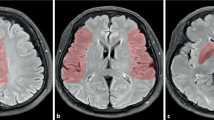

Magnetic resonance imaging morphometry

The measurement of temporomesial volume by volumetric MRI (the protocol includes T2-weighted and proton density-weighted images, MRA, and three-dimensional T1-weighted sequences) [77], especially the hippocampal formation, can provide important information on cognitive performance [78]. Lesions affecting the bilateral medial temporal lobes typically lead to severe memory deficits. Unilateral lesions in the dominant hemisphere can cause deficits in verbal memory, while unilateral lesions in the nondominant hemisphere can cause visual'spatial memory loss. Aneurysmal SAH was shown to be associated with temporomesial atrophy, especially after surgical clipping [76]. Temporomesial volume loss is correlated with neuropsychological impairment, which includes memory deficits [78].

Bendel and colleagues examined the impact of brain structure volume changes on neurocognitive performance by evaluating the MRI scans of 138 patients that were randomly assigned to surgical versus yearvascular treatment 1 year after the haemorrhage. Reduced hippocampal volume correlated with poor score on several measures of cognitive function such as visual memory, attention, flexibility of mental processing, intellectual ability, and psychomotor speed [78]. These deficits are more pronounced in patients who have combined decreased hippocampal volume and frontal lobe lesions, and are more common after surgical clipping than endovascular coiling [79].

The same group described the relationship of global cerebral atrophy and cognitive deficit after SAH [80 y yearenty-six patients (1 year after haemorrhage) and 30 healthy controls underwent MRI (T2-weighted and proton attenuation-weighted images, and three-dimensional T1-weighted images needed for volumetry). The cerebrospinal fluid/total intracranial volume ratio was quantified by statistical parametrical mapping, and was statistically higher in SAH patients and correlated with clinical outcome (that is, Glasgow outcome scale) and cognitive deficit.